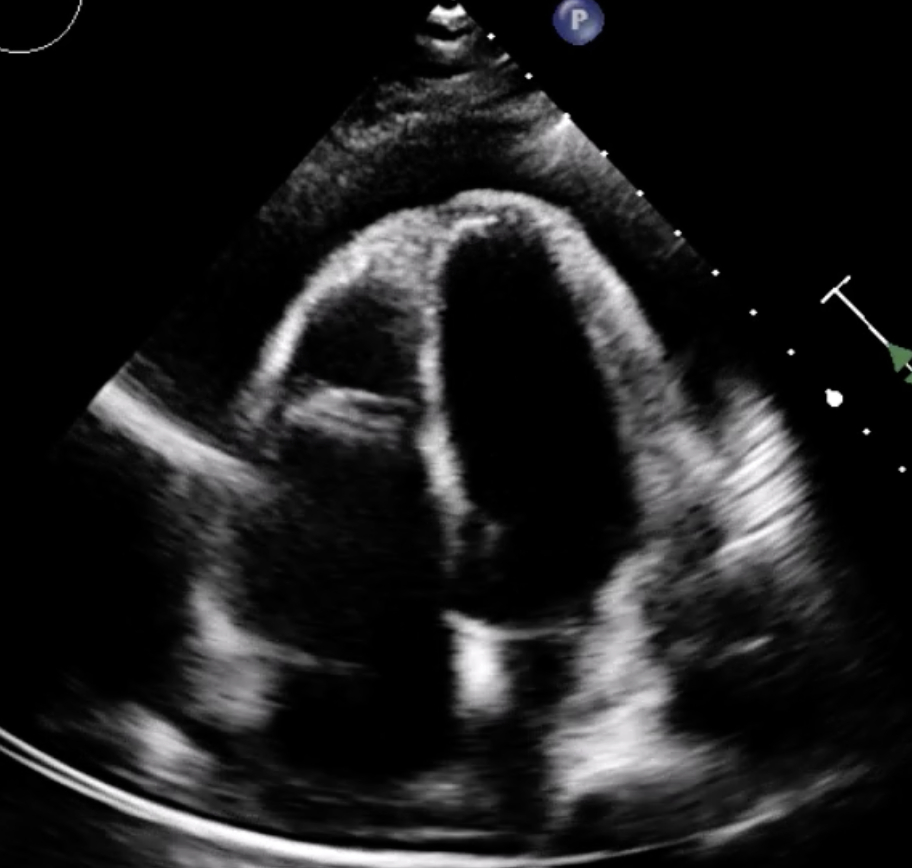

Abstract Body (Do not enter title and authors here): Case Presentation: A previously healthy 33-year-old woman developed acute pericarditis with early tamponade physiology following a Coxsackievirus B infection contracted from her child. Despite urgent pericardiocentesis (550 mL) and standard anti-inflammatory therapy with NSAIDs and colchicine, she progressed to incessant pericarditis necessitating corticosteroids.

Rilonacept was initiated at week 7 due to persistent steroid dependence. Within 4–6 weeks, the patient achieved complete clinical remission, normalization of inflammatory markers, and resolution of echocardiographic abnormalities. Corticosteroids were successfully discontinued over a 3-month taper while maintaining remission on rilonacept at 21-week follow-up.